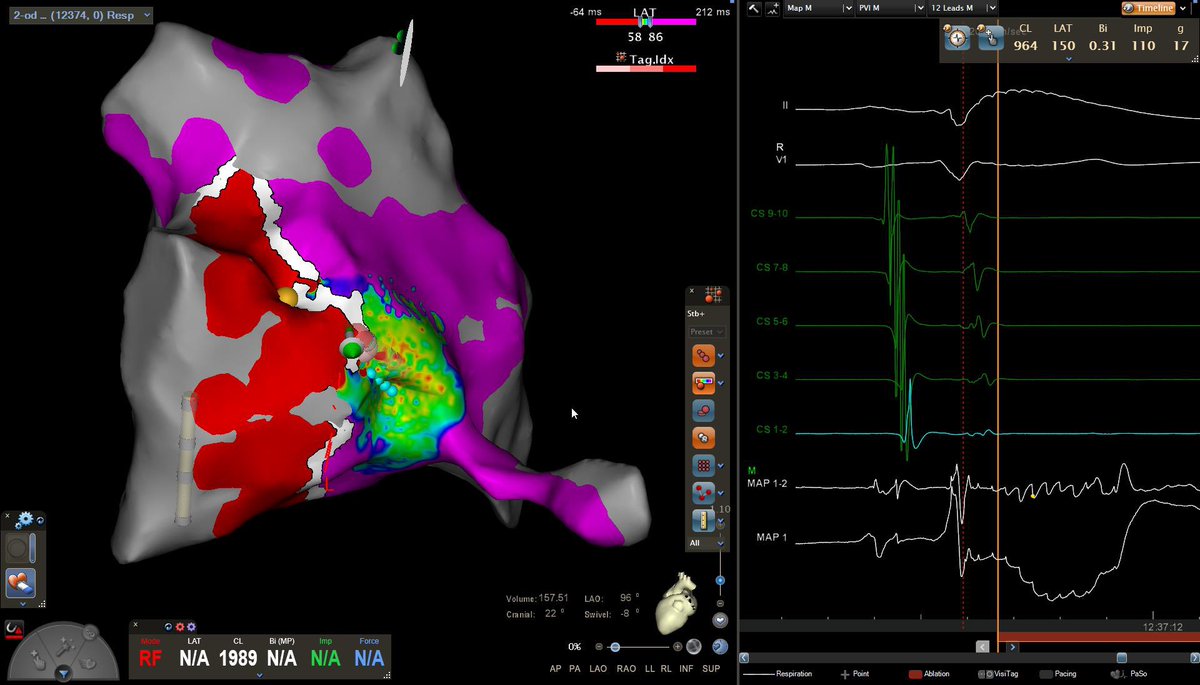

Impact of Left Atrial Posterior Wall Isolation using Pulsed-field Ablation in Patients Undergoing Repeat Catheter Ablation for Atrial Fibrillation #OpenAccess heartrhythmjournal.com/article/S1547-…